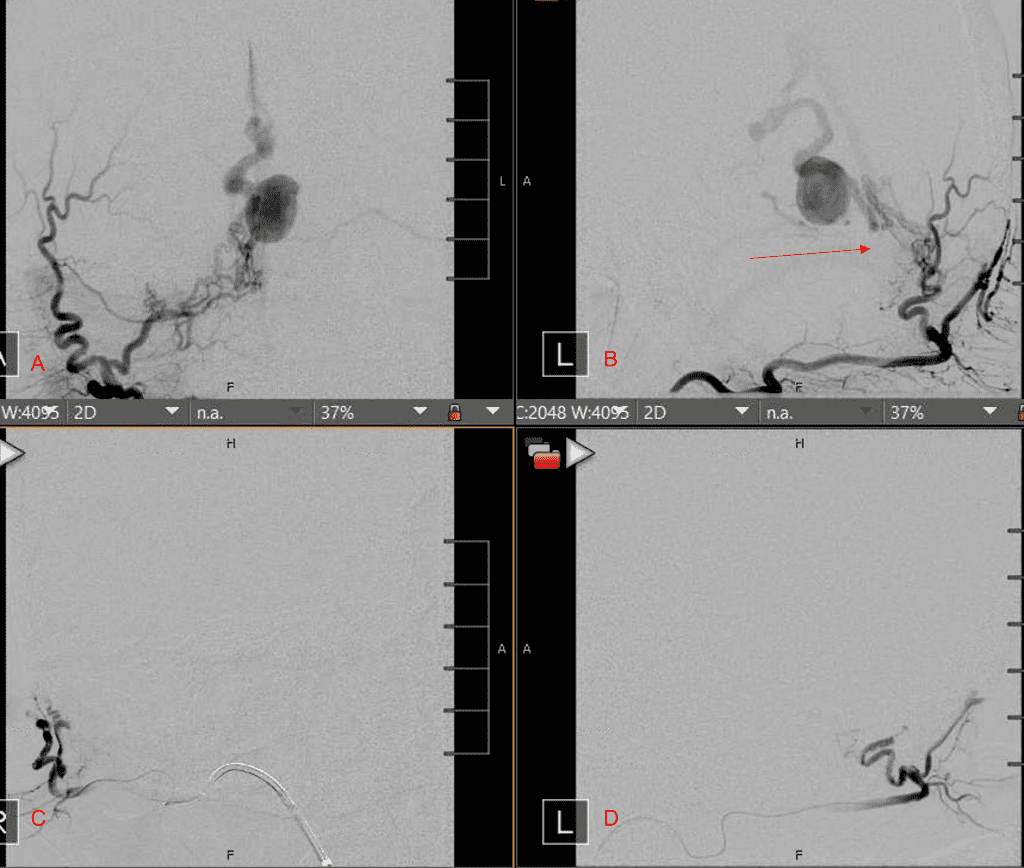

Figure 4. Left ECA AP and Lateral angiograms Pre (A and B) and Post NBCA embolization (C and D) Demonstrate near complete obliteration of Left Occipital Artery Fistulas.

Embolization was successful at immediately reducing the pressure into the Aneurysmal Varix with greater than 90% reduction in A-V shunts. After an intensive period of critical care monitoring and care for her initial brain hemorrhage, she made a near complete recovery with mild intermittent left sided paresthesias and generalized deconditioning. After receiving inpatient and outpatient Acute Rehabilitation, Physical, and Occupational therapy, she completely recovered all of her Activities of Daily Living (ADLs) at 3 months and achieved an modified Rankin Scale (mRS) of 0. On follow-up angiography, small residual low flow A-V shunts were identified and targeted for Gamma Knife Radiosurgery (Figure 5 and 6).